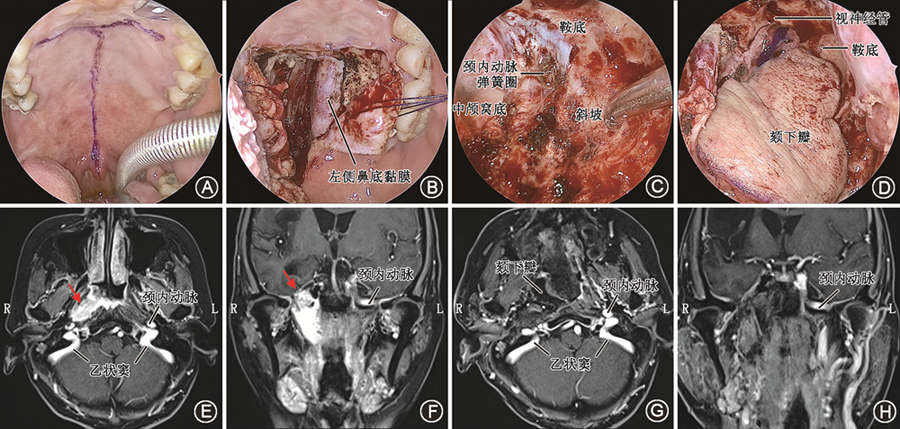

3. 内镜经口翼突后入路(联合入路):内镜经口翼突后入路适用于病变广泛侵犯颅底中线区域和侧方区域的病变,如晚期的复发性鼻咽癌、颅底恶性肿瘤等。该入路经口行大问号切口。切开咽上缩肌进入咽旁间隙,通过茎突肌群定位咽旁段颈内动脉,确定安全边界。在经鼻入路中,需要磨除翼突才能自前向后显露上述解剖结构。而在内镜经口翼突后入路中,在翼内肌和咽上缩肌之间通过下咽旁间隙至翼突后,从翼突后方即可显露上述解剖结构。避开翼突,通过咽旁间隙这一固有解剖间隙直达颅底,不仅创伤小、出血少、省时省力,而且因为保留了翼内肌和翼外肌,可以最大化地保护患者的咀嚼功能。该入路以最直接的径路到达岩斜区、颈静脉孔区,在确保风险可控的前提下,可以最大范围地显露岩斜区和颈静脉孔区,同时最大程度地保护翼内肌和翼外肌(图6)。

2. 术前检查与颈内动脉预处理:术前应行增强CT和增强MRI检查,如果肿瘤累及颈内动脉或颅内,可选择在复合手术室进行手术。复杂性侧颅底肿瘤手术需要多学科诊疗团队成员协同参与,建议邀请神经外科和介入科医生参与手术。应常规进行颈内动脉球囊闭塞试验(balloon occlusion test,BOT),评估阻塞患侧颈内动脉后脑侧支的循环代偿功能[11]。对于肿瘤与颈内动脉尚可分离的患者,可在DSA护航下手术。对于肿瘤与颈内动脉无法分离的患者,如果BOT阴性,可以考虑颈内动脉栓塞;如果BOT阳性,需要先行颅内外血管搭桥,再行颈内动脉栓塞,或置入颈内动脉覆膜支架。

3. 手术策略:根据病变位置选择合适的切口。若病变主体位于中线的鼻咽区、咽鼓管区,可采用内镜经口经腭入路;若病变主体位于侧方的神经血管区、颞下区,可采用内镜经口经翼下颌皱襞入路;若病变广泛侵犯颅底中线区域和侧方区域,可采用内镜经口经翼突后入路。无论采用何种入路,都应采用广暴露的原则,尽可能大范围地显露周围重要结构,如颈内动脉、颈内静脉、后组颅神经等。广暴露的目的是充分保护好这些结构,术后根据颅底缺损的大小进行妥善修复。与内镜经鼻颅底手术相比,内镜经口侧颅底手术应注意伤口愈合不良导致的腭瘘,建议术中对切口分层缝合,术后鼻饲饮食以避免经口饮食造成的伤口感染。

4. 术后随访:外科手术应强调肿瘤全切,同时注意综合治疗的重要性。对于恶性肿瘤,术后应根据切缘情况结合MRI,给予综合治疗。对于切缘阴性、MRI未见残留的恶性肿瘤,应密切随访。对于切缘阳性、MRI显示有肿瘤残留的恶性肿瘤,建议补充靶向药物、免疫药物进行治疗。